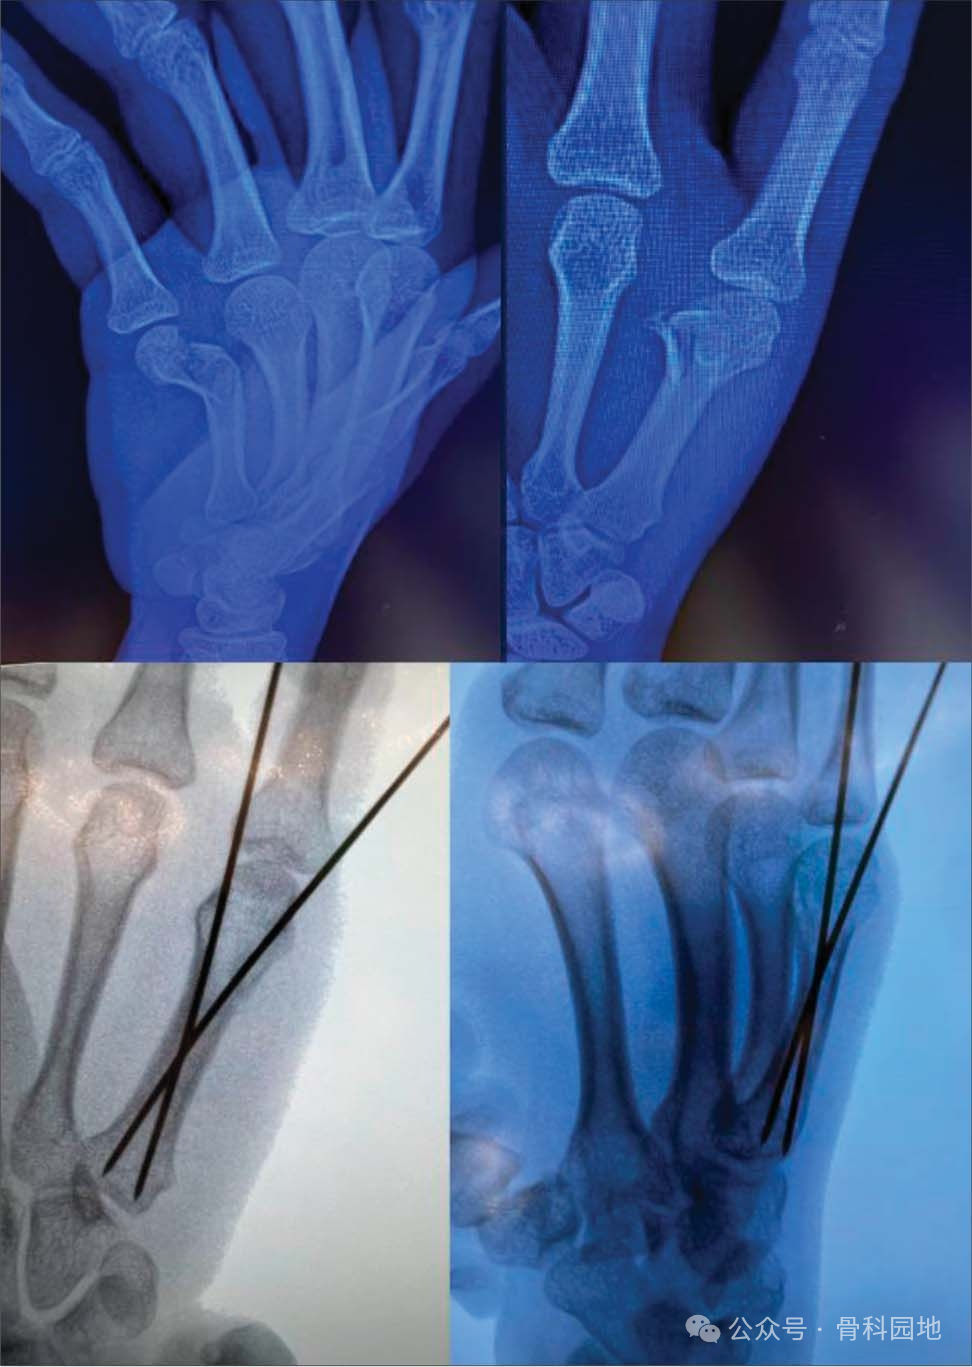

四、掌骨基部骨折

第一掌骨基部骨折对非手术治疗的耐受性更高,因为腕掌骨关节代偿。手术选择包括经皮闭合复位与切开复位和内固定技术,包括骨折间螺钉、钢板和螺钉结构或髓内固定。